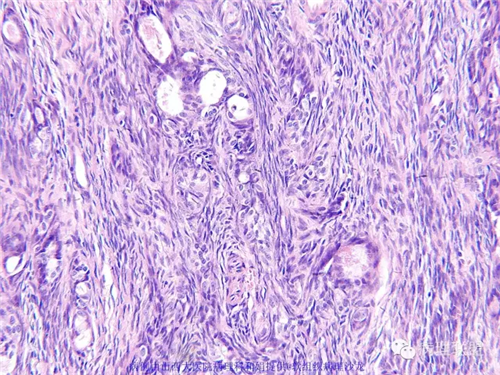

M,57岁,右膝关节外侧皮下肿物10余年,活动度好。

本例形态学上是非常典型的双相型滑膜肉瘤,滑膜肉瘤临床上大部分表现为生长缓慢的肿瘤。以青壮年多见,主要发生于四肢大关节附近,也可见于其他少见部位,如肺、肾等实质器官,形态学分为5种类型:单相纤维型、单相上皮型、双相型、低分化梭形细胞型和小细胞型。有文献报道个别患者有长达20年的病史。